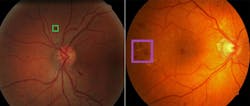

To the left is a retina containing a lesion, known as an exudate (inside the box), associated with diabetic retinopathy. To the right is a retina containing a lesion known as a hemorrhage, which is also associated with diabetic retinopathy.